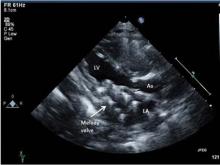

At a median follow-up of 8 months, regurgitation on the echocardiogram was considered to be mild or less in all patients. The median gradient was 3 mm Hg (range, 2-7 mm Hg) on the immediate postoperative echocardiogram. Three patients developed a mild paravalvular leak; one of these patients had undergone aggressive stent resection, a modification Dr. Emani does not recommend. One patient developed left ventricular outflow tract obstruction (LVOTO), which Dr. Emani attributed to the lack of distal stent fixation in this patient. Another patient with an AVC defect developed complete heart block.

Dr. Emani offered some procedural tips. First, the Melody valve must be optimized for surgical implantation in infants. The length of the valve must be reduced by trimming it to reduce the chance of LVOTO or pulmonary vein obstruction. He recommends sizing the valves by echocardiogram and fixating the distal stent to the inferior free wall of the ventricle.